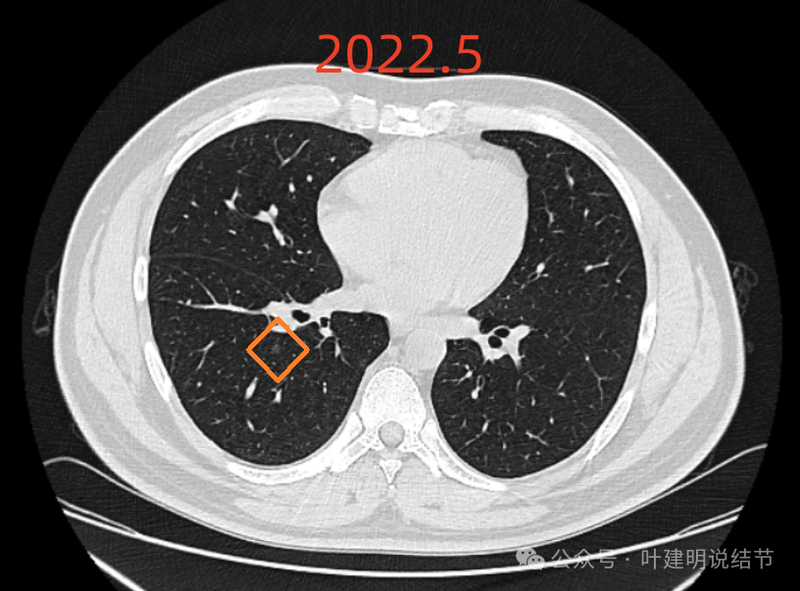

提供的影像资料是从2022年5月始的:

右下叶微小磨玻璃结节,密度很淡,轮廓较清,肯定没有实性成分。